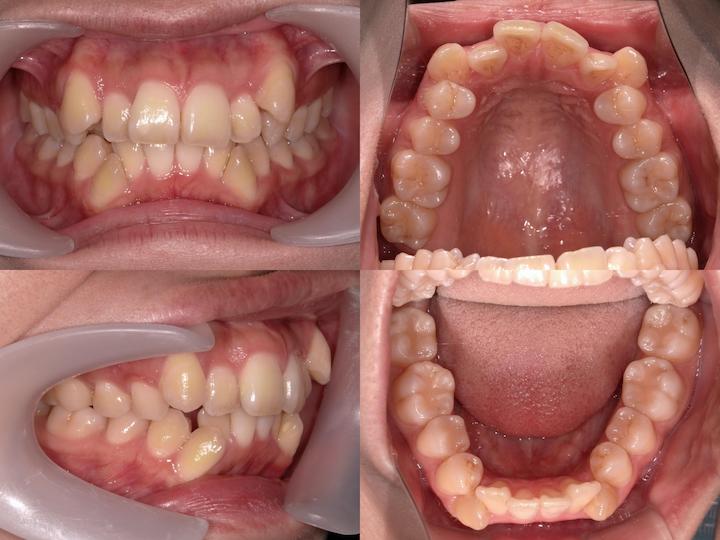

本症例は、上下顎前歯部の著しい叢生および犬歯の低位唇側転位(八重歯)を主訴とする患者様に対し、上下顎ともに舌側矯正装置を使用して治療を行いました。

高度なアーチレングスディスクレパンシーを改善するため、上下小臼歯の計4本を抜歯し、適切な咬合関係の確立を図りました。

また、AngleⅡ級臼歯関係の改善を目的として、下顎大臼歯を近心移動する治療計画を採用しました。

主訴:上下前歯部の叢生および犬歯の低位唇側転位(八重歯)

初診時の口腔内所見として、以下の不正咬合が認められました。・上下顎前歯部の重度叢生

・犬歯の低位唇側転位(八重歯)

・著しいアーチレングスディスクレパンシー

・AngleⅡ級臼歯関係(下顎大臼歯の後方位)

・口唇部の突出感は認められない